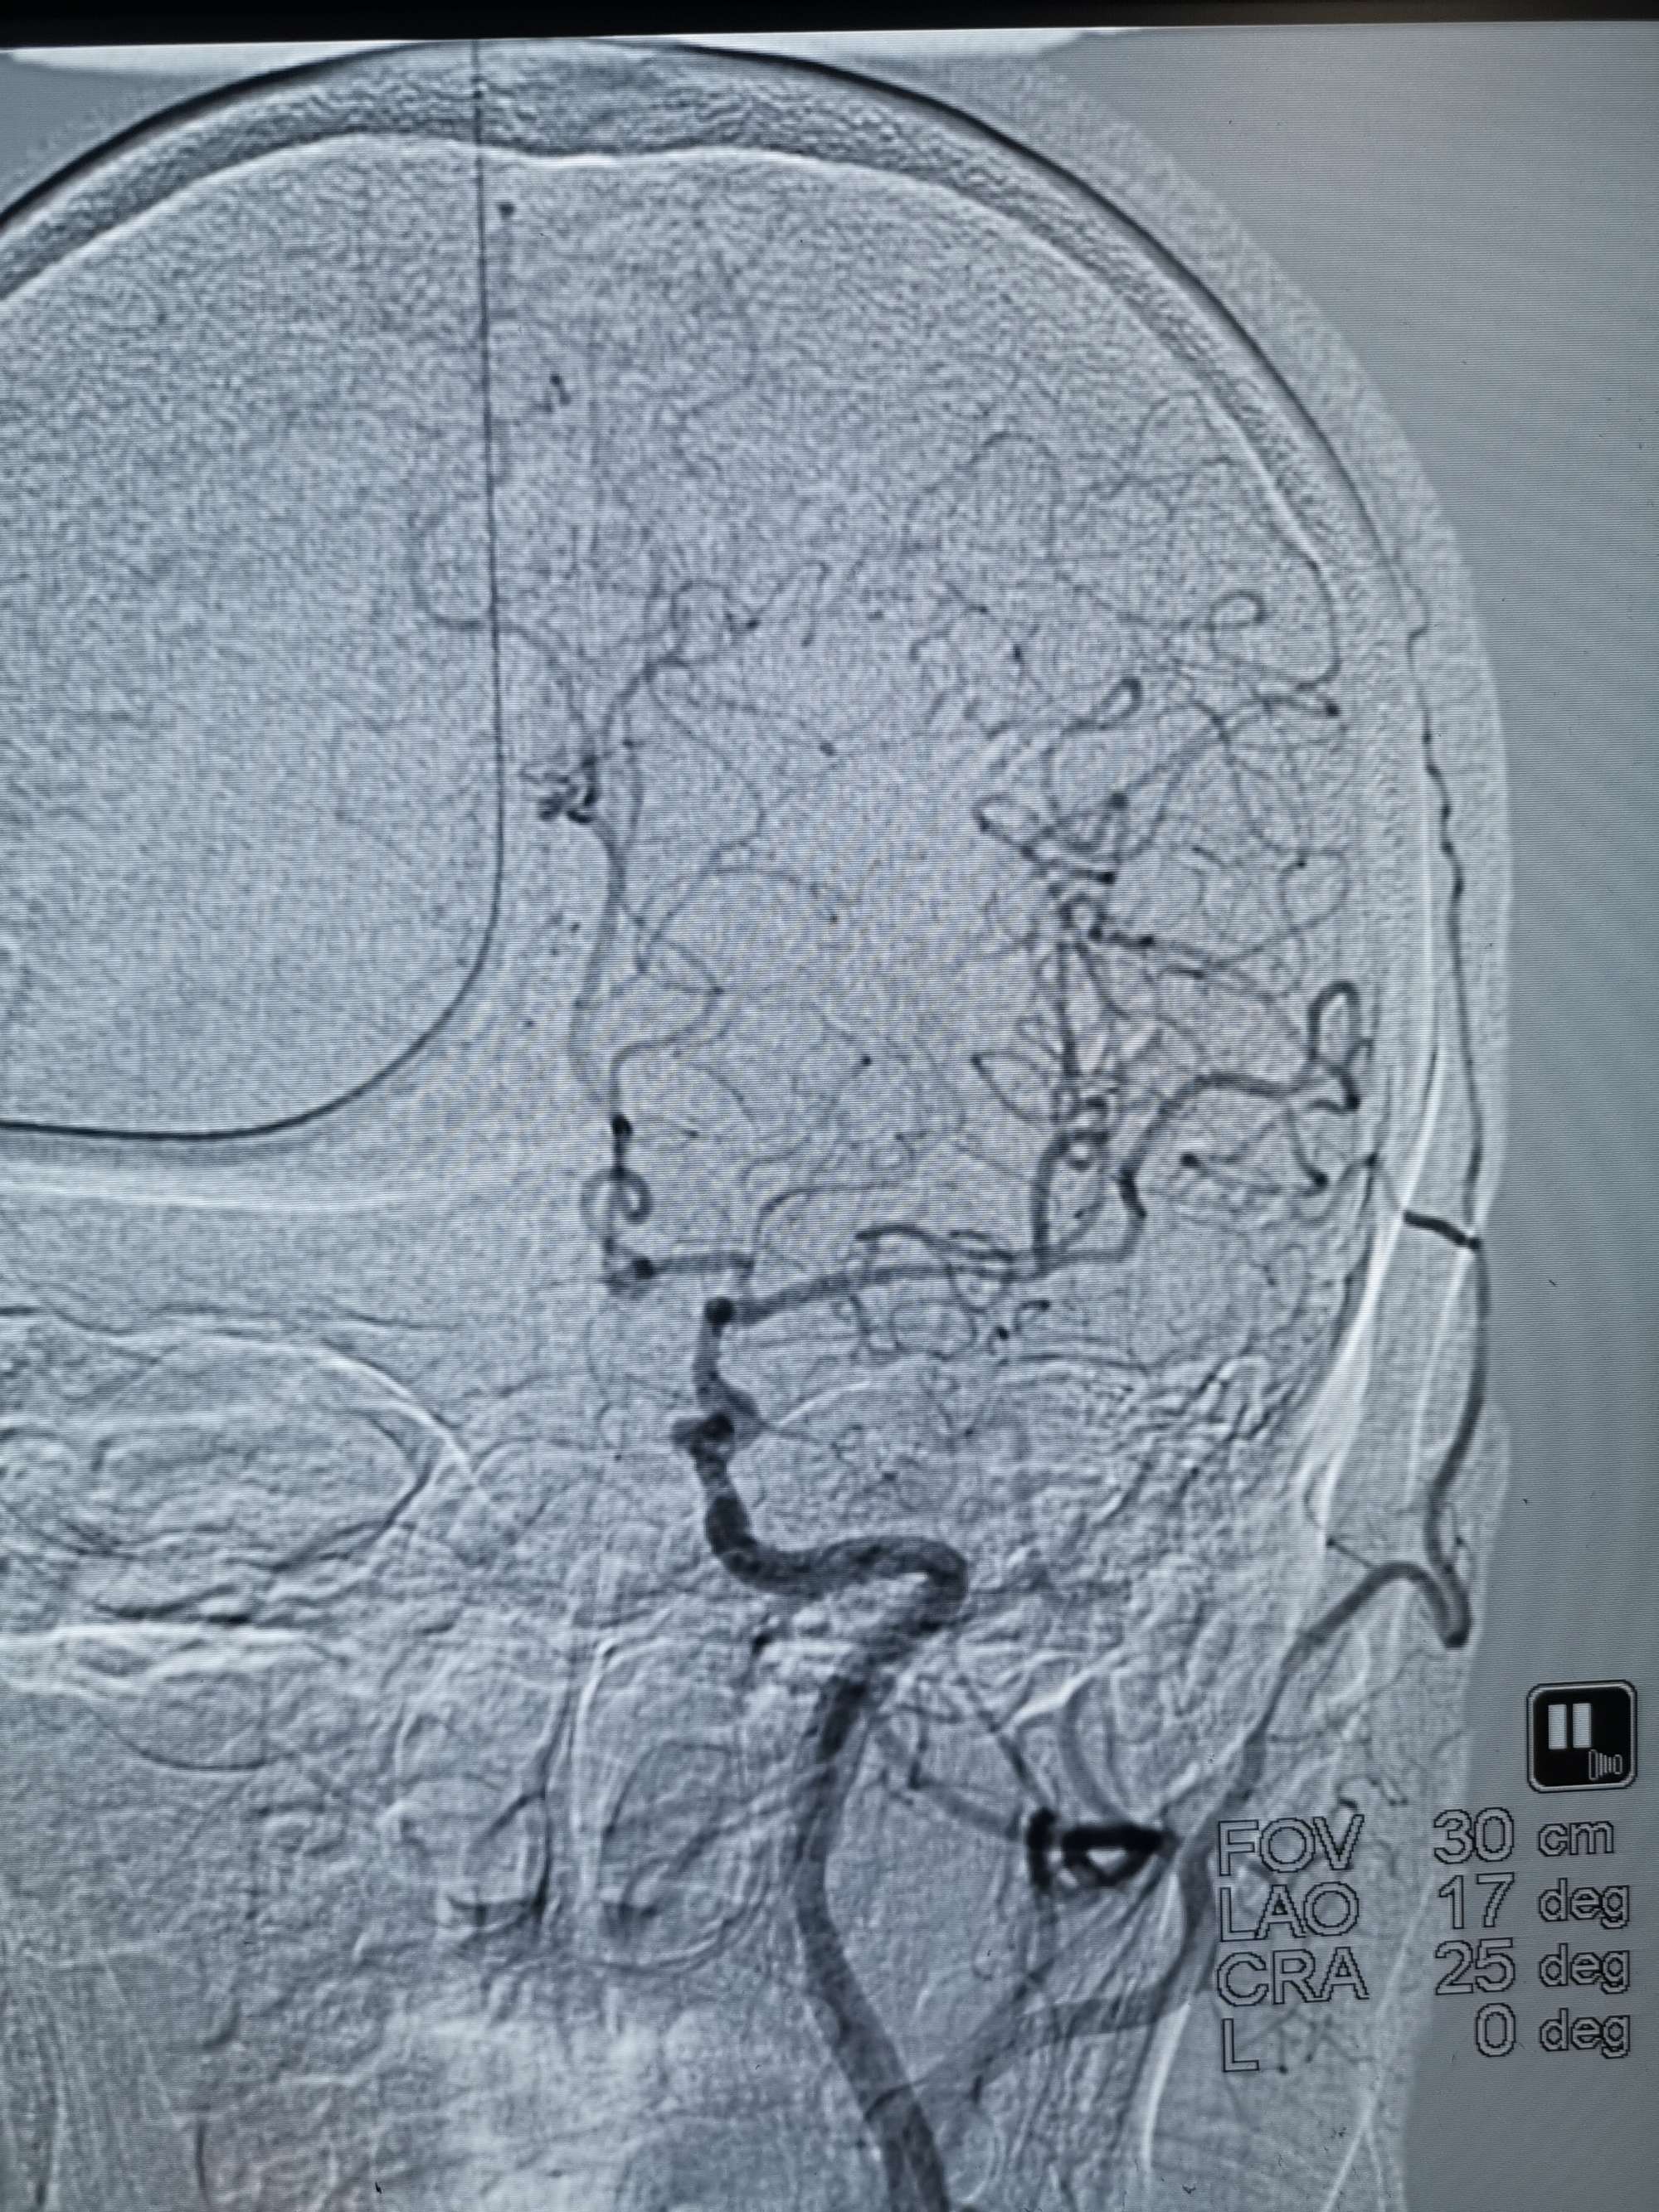

手术过程

在微导管支撑下先将微导丝和微导管穿过闭塞段,微导管超选造影证实位于基底动脉真腔后更换300cm外周交换导丝,撤出微导管后按从小到大,从远到近的原则行球囊扩张,本例手术选择了1.5✖️15、2.0✖️20、2.5✖️20球囊进行扩张,扩张满意后植入Enterprise支架,手术结束。

术后造影见左侧椎动脉闭塞段管腔恢复正常直径,远端血运良好。